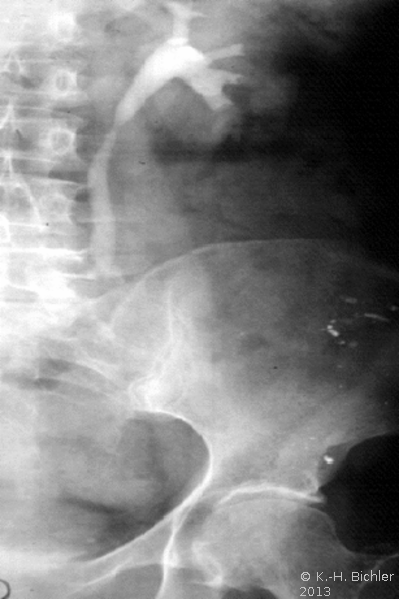

- Abbildung Harnleiterkarzinom (Urothel) links Mitte:

- a) Ausscheidungsurogramm: Abbruch der "Kontrastmittelstraße"